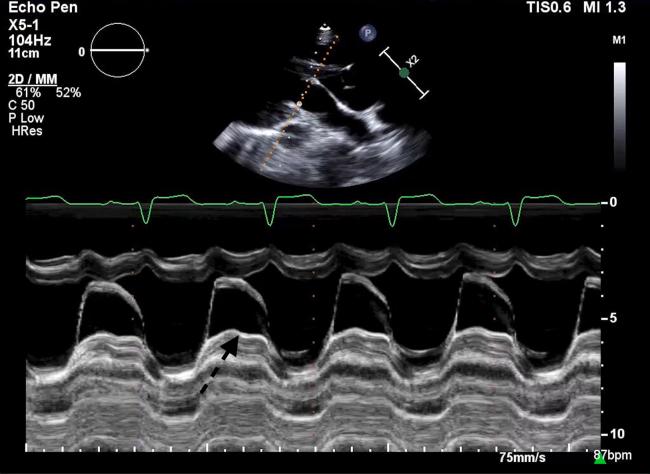

Unileaflet Mitral Valve in Patient With Marfanoid Habitus.

• Unileaflet mitral valve is a very rare congenital heart condition. • It is usually lethal in neonates with severe regurgitation. • Rare asymptomatic cases can be diagnosed later in life.